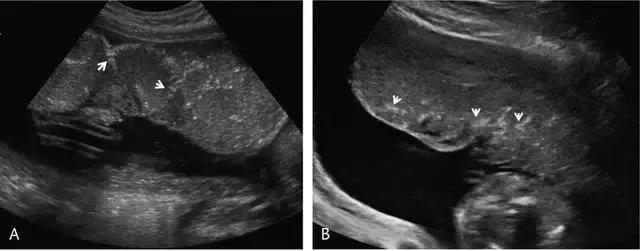

前置胎盘指胎盘覆盖于宫颈内口或位于宫颈内口 2 cm 之内,是晚孕时无痛性阴道出血的重要原因。既往,曾根据胎盘距离宫内口的远近分级为完全性、部分性、边缘性和低置胎盘(图 10)。

2012 年美国妇产科协会对前置胎盘的分类进行了修订,认为边缘性与部分性前置胎盘难以区分,建议只在描述胎盘边缘相对于宫内口的位置。

图 10 示前置胎盘:A 为各种前置胎盘示意图,分别为低置、边缘性、部分性和完全性。B 为孕 20 周的完全性前置胎盘纵切面,箭头示胎盘完全覆盖于宫内口。C 为另一例孕 33 周胎儿的矢状位 T2WI ,星号指胎盘完全覆盖于宫内口。D 为孕 12 周时的低置胎盘矢状面,长箭头示胎盘下缘,短箭头示宫内口,二者距离< 2 cm

推荐经阴超测量胎盘下缘至宫内口距离,若无阴超探头,可选择经会阴超声检查。通常,经腹部超声检查可因胎头覆盖于子宫下段、母体肥胖、膀胱过度充盈或充盈欠佳导致测量不精确。